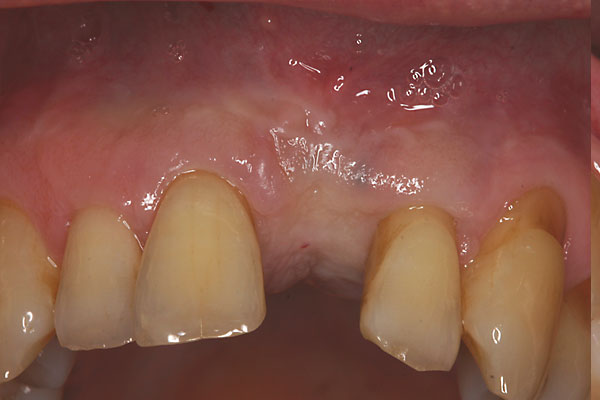

Fall: Einzelzahnlücke nach Zahnextraktion